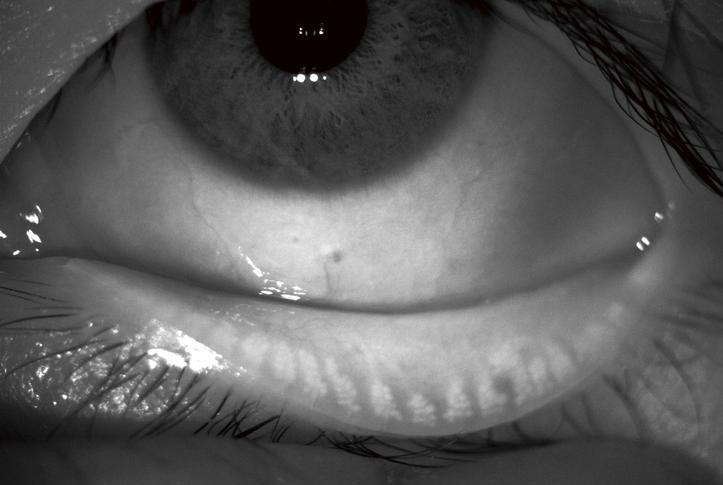

Excessive evaporation of your tears is the commonest reason that your eyes feel dry, and this is due to poorly functioning, and blocked tear glands (meibomian gands) within your eye lids

The skin around the eyes is cleaned and any make up removed in advance. A special contact lens is placed in each eye for protection against the bright flashes. Clear gel is spread over the treatment area, and the pulses of light are applied in a row from ear to ear, and over the eye lids. Sometimes a massage of the eye lids is then performed to encourage the flow of tears.